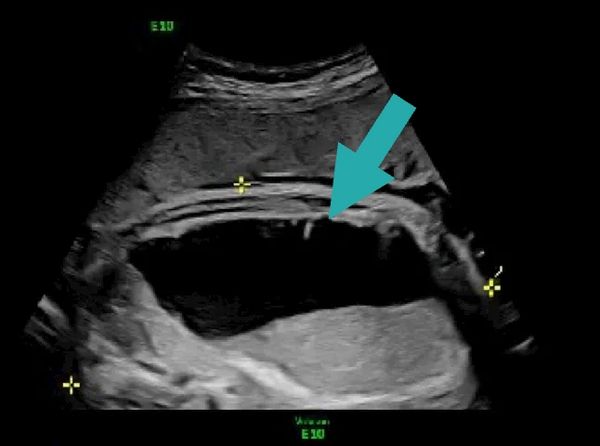

(Pic: fetal ultrasound with arrow demonstrating intraabdominal cyst)

An intra-abdominal cyst is a fluid-filled structure, much like a little ballon, identified in the baby’s abdomen on prenatal ultrasound. These cysts are relatively uncommon and most are benign. The outcome depends on the cyst’s size, location, appearance, and behavior over time.